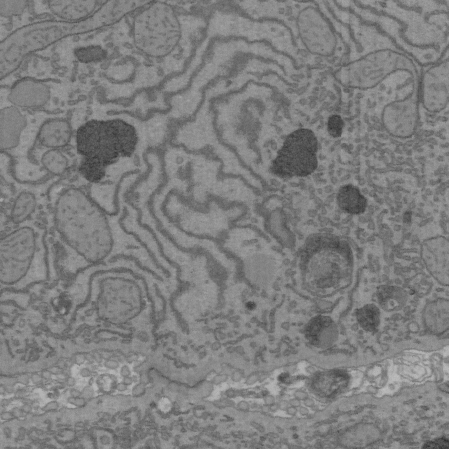

Datasets. We used the “BetaSeg” [22] dataset111http://betaseg.github.io, which was made publicly available by the authors. This Focused Ion Beam Scanning Electron Microscopy (FIB-SEM) dataset captured primary mouse pancreatic islet β\beta cells at a 16 nm isotropic resolution. The final dataset consists of two groups of high and low glucose cells and also provides human curated binary segmentation masks for seven subcellular structures, i.e. centrioles, nucleus, plasma membrane, microtubules, golgi body, granules, and mitochondria. Consistent with [34], we also chose the 4 high glucose cells for this work. For evaluation, cells 1, 2, and 3 from four cell volumes of high glucose were used for training, while cell 4 served as an independent test set.

Next, we used the “liver FIBSEM” dataset, which consists of samples that were fresh needle biopsies fixed with 4%PFA and 2%GA in phosphate buffer. High contrast staining was performed with reduced osmium and Waltons lead aspartate stain [33] and embedded in Epon. Sample preparation and imaging were done on a ZEISS GeminiSEM according to prior reports [35]. The final dataset consists of one cell volume with 1111 crops that have been extracted from a cell volume, annotated manually, and used for training, validation, and testing. The segmentation masks consist of six subcellular structures, mitochondria, peroxisomes, lipofuscin, basolateral membrane, open bile canaliculi, and closed bile canaliculi, along with an additional “background” category.

While it is true that FIB-SEM datasets like “BetaSeg” [22] offer isotropic resolution suitable for 3D processing, this is not always the case in EM imaging, where data often come in 2D slices (especially in higher-throughput screens).